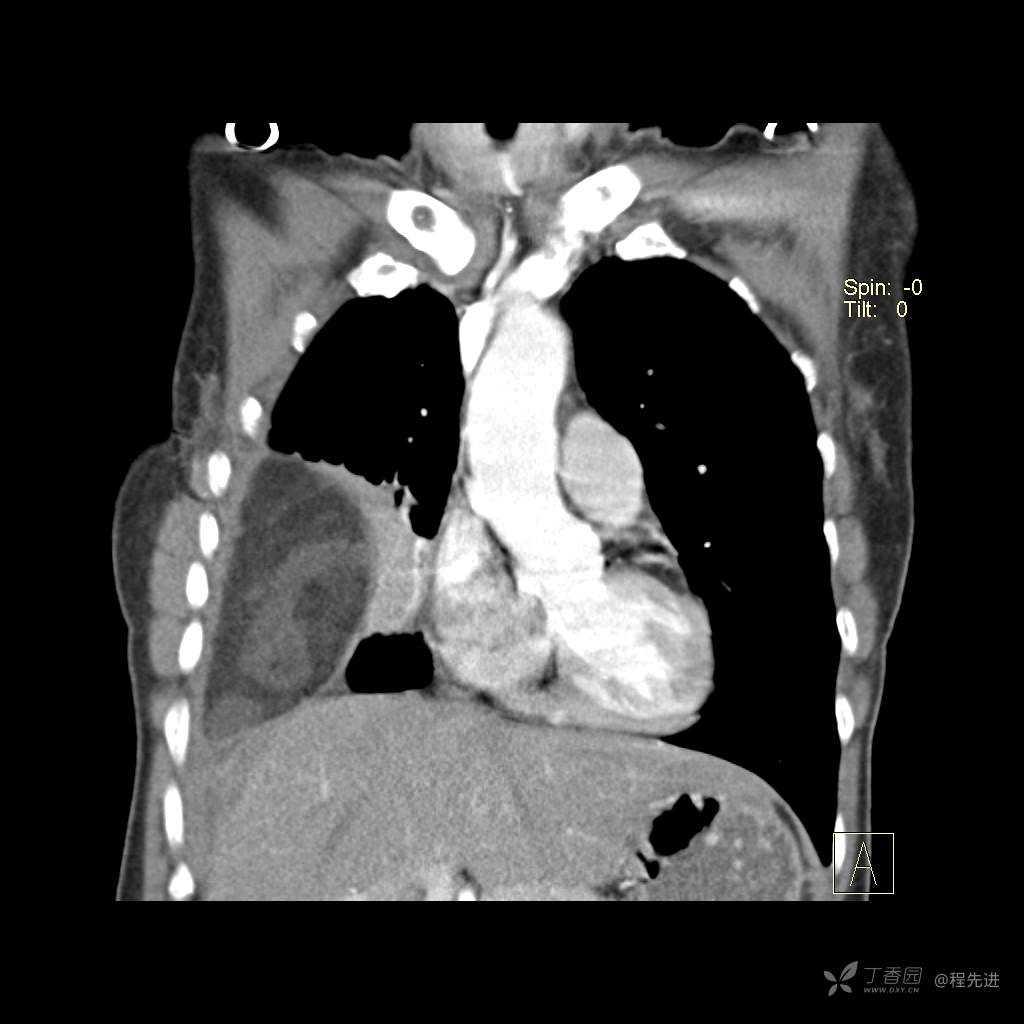

患者性别:女

患者年龄:51岁

简要病史:胸闷半年

肺淋巴管肌瘤病 (7)

乳糜胸 (8)